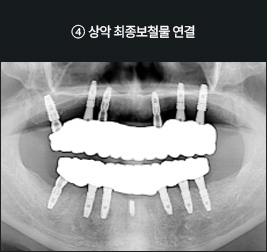

I      올온포 풀아치 임플란트 사례      I

치료 기간 : 2021.03.12 ~ 2021.08.25

치료 기간 : 2021.06.05 ~ 2021.12.10

I      올온식스 풀아치 임플란트 사례      I

치료 기간 : 2021.05.08 ~ 2021.11.19

치료 기간 : 2022.05.17 ~ 2022.12.05

I      올온믹스드 풀아치 임플란트 사례      I

치료 기간 : 2023.07.25 ~ 2024.02.03

치료 기간 : 2023.11.14 ~ 2024.05.28